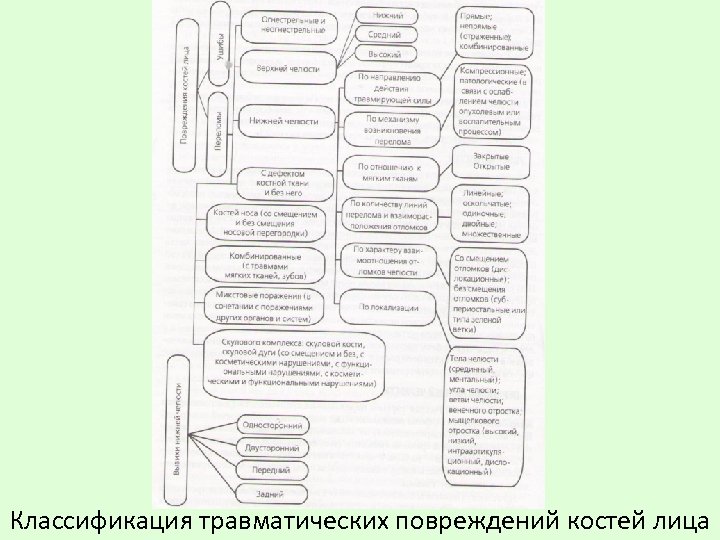

Классификация травматических повреждений костей лица